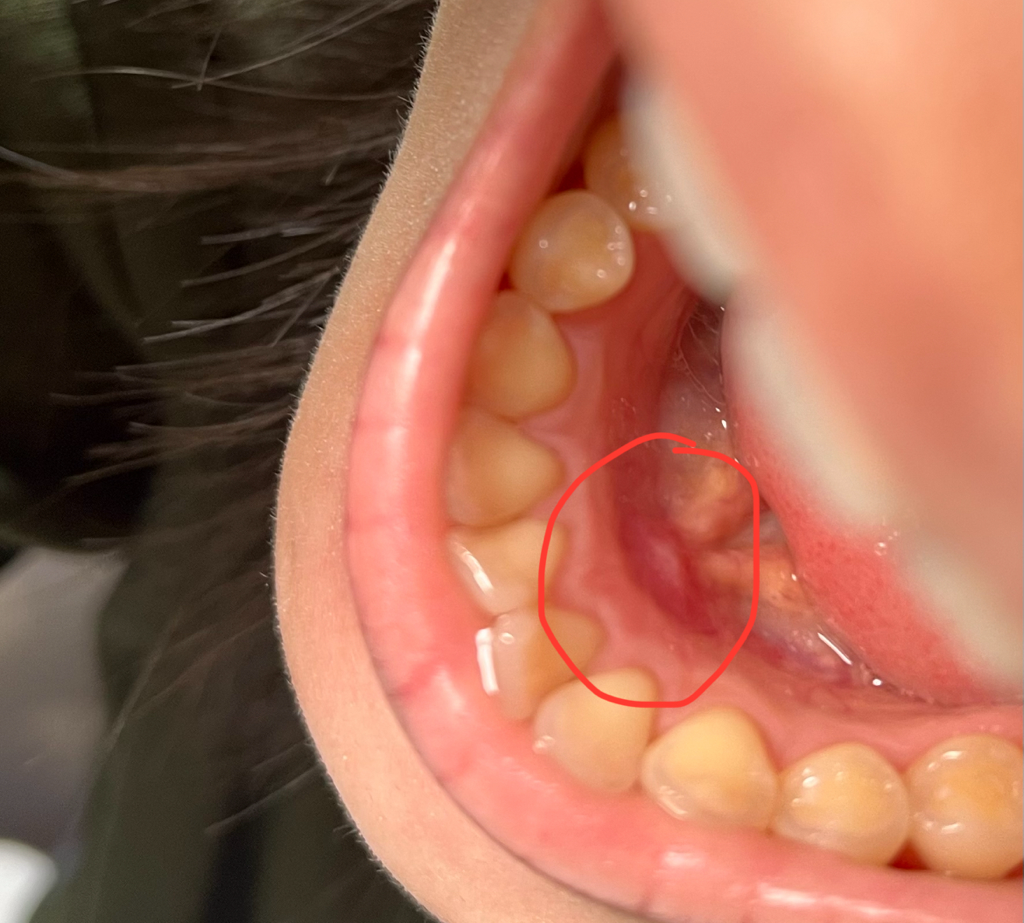

잇몸에 흰색 딱딱한게 났는데 큰 병원 가봐야 할까요

거의 반년정도 됐는데 잇몸에 흰색 딱딱하고 동그란 혹같은게 생겼어요 옆으로 밀면 안에 있는 흰색 덩어리가 옆으로 움직여서 좀만 더 힘주면 아예 밖으로 튀어 나올 것만 같은데 큰 병원 가봐야 하나요,,, 오랫동안 안 없어져서 걱정이에요

영상이나 사진으로 보아서는 정확한 판단이 어려워 보입니다. 치과를 방문하여 dental-ct 등의 촬영이 필요할 것으로 보이며 문제가 된다면 절개를 하고 해당 부위를 제거하는 것이 필요할 수도 있어 보입니다. 가까운 치과를 방문해보시길 바랍니다.

사진에 보이는 부분은 잇몸뼈가 튀어나온거 같습니다 .큰 문제가 잇는건 아니니 걱정하지 않으셔도 될것같습니다.

문의주신 사진상 골융기 증상으로 의심이 되며, 만약 불편감이 있는 경우에는 치과에 방문하여 상태를 확인후에 제거수술을 받길 권합니다.